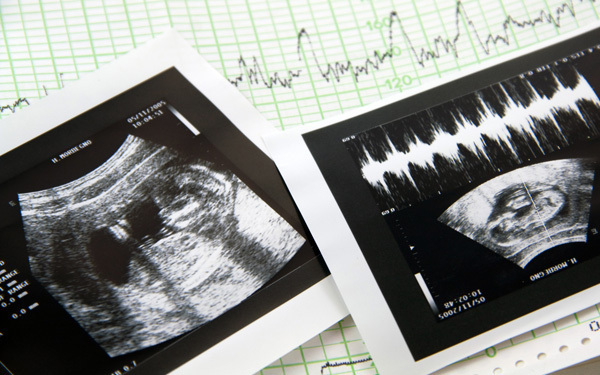

新生児と同じくらいすべての器官が完成

ほとんどの器官が完成

ここまで育てば早産でも無事育つことができます。しかし、早産の赤ちゃんには合併症の心配などがあります。